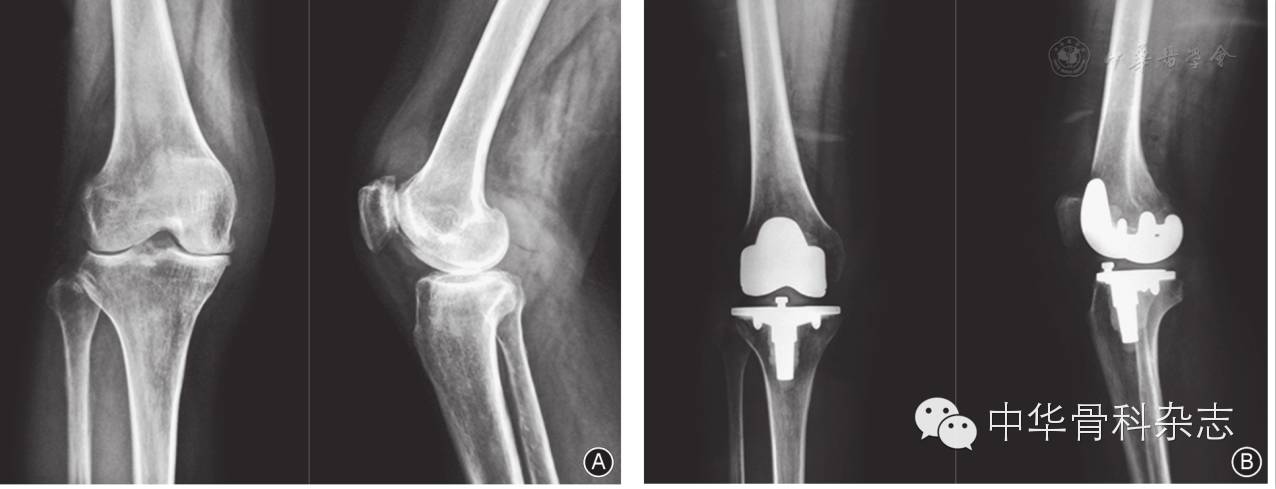

固定平台组与旋转平台组患者的膝关节活动度由术前72.8°±13.1°和71.2°±12.8°提高至末次随访时106.5°±9.8°和115.4°±7.9°,差异有统计学意义(P<0.05,表2)。X线股胫角由术前16.8°±5.3°和15.2°±4.7°降至末次随访时5.6°±2.3°和5.2°±2.1°;HSS膝关节评分由术前(47.5±7.1)分和(49.6±8.9)分提高至末次随访时(89.1±4.6)分和(90.2±5.3)分;SF-36评分由术前(52.3±15.4)分和(50.1±17.9)分提高至末次随访时(81.6±12.3)分和(82.2±14.5)分,差异均有统计学意义(P<0.05,表2图1图2)。

图1 女,41岁,右侧膝关节骨关节炎伴外翻畸形 A 术前右膝正、侧位X线片示关节间隙明显狭窄,胫股角19° B 应用固定平台假体全膝关节置换术,术后正、侧位X线片示下肢力线及假体固定良好